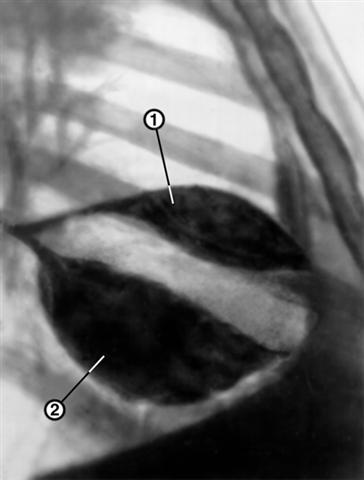

Рис. 6. Рентгенограмма органов грудной клетки больного с правосторонним междолевым плевритом (правая боковая проекция): линзообразные тени выпота в горизонтальной (1) и косой (2) междолевых щелях правого легкого.